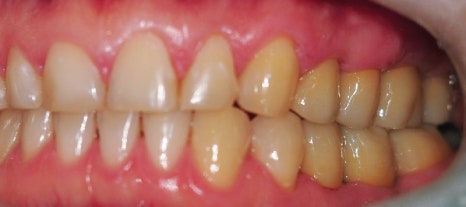

먼저 초진 구강 사진부터 보도록 하겠습니다.

▶초진 구강 사진

▲ 초진구강사진

충치로 인하여 뿌리만 남아있는 치아들과 심지어 자연 발치된 치아도 확인해 볼 수 있습니다.